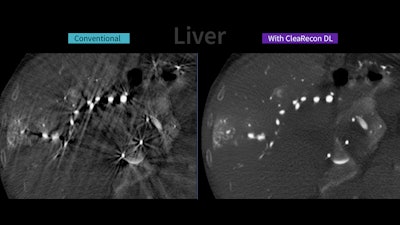

Images compare CBCT liver images with and without the CleaRecon DL system.GE HealthCare

The system is designed to remove streak artifacts caused by pulsating blood flow in the arteries and changes in contrast distribution during CBCT image acquisitions in the liver, prostate, brain, and endovascular aortic repair procedures.